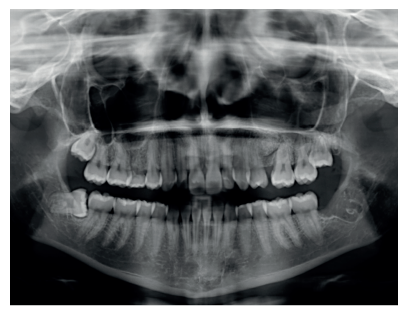

Se presenta un caso clínico de una mujer de 20 años de edad, que acudió remitida por su ortodoncista para la extracción de un premolar retenido maxilar, en posición invertida, previo a la realización de tratamiento ortodóntico. Se realizó la Historia Clínica de la paciente, que no presentó antecedentes médico-quirúrgicos de interés, alergias medicamentosas conocidas ni hábitos nocivos. A la exploración extraoral no se apreció ningún dato relevante. A la exploración intraoral, la paciente presentó la ausencia en boca del segundo premolar superior izquierdo y la presencia de los terceros molares inferiores retenidos (Figuras 1, 2 y 3).

A la exploración radiográfica mediante radiografía panorámica se apreciaron ambos terceros molares inferiores retenidos, en una posición mesioangular, los superiores retenidos en posición vertical y la presencia de un premolar maxilar retenido, en posición invertida, en el segundo cuadrante (Figura 4).